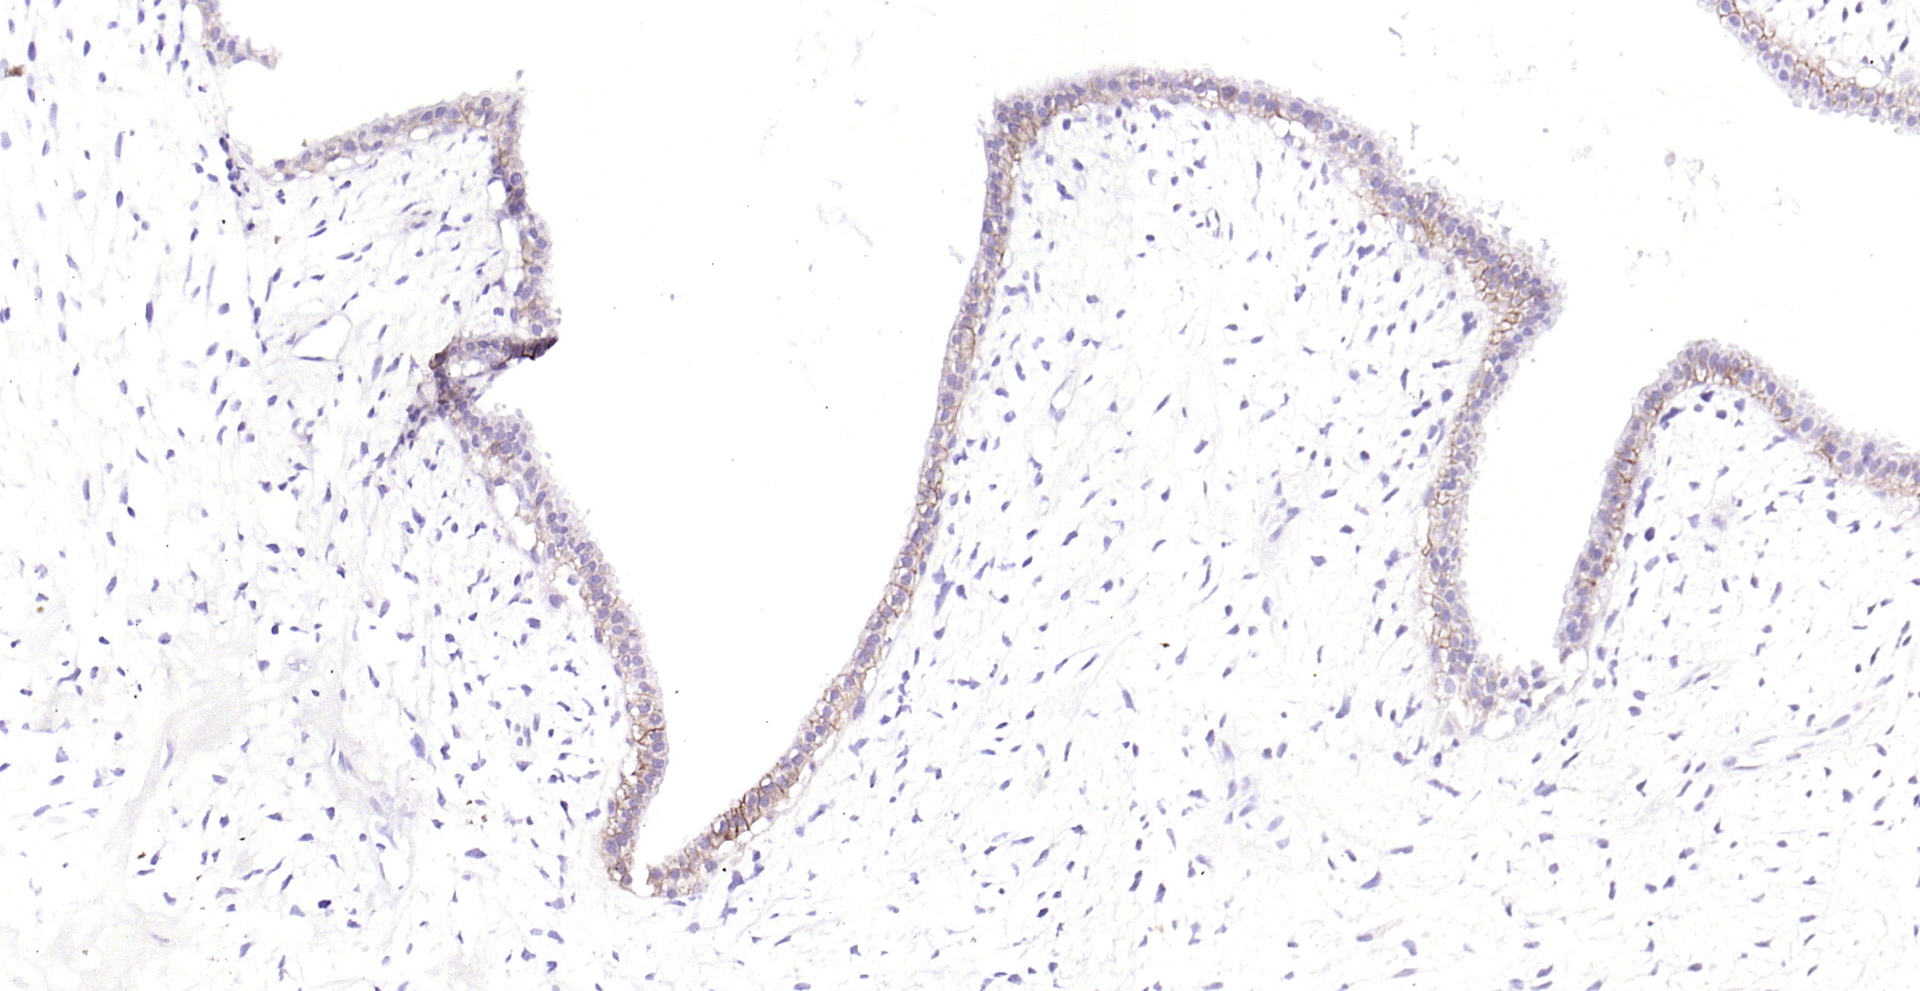

Product Name CD239 Recombinant Antibody

Applications WB, IHC-P, IHC-F, IF(IHC-P)

IHC-P IHC-P1:100-500